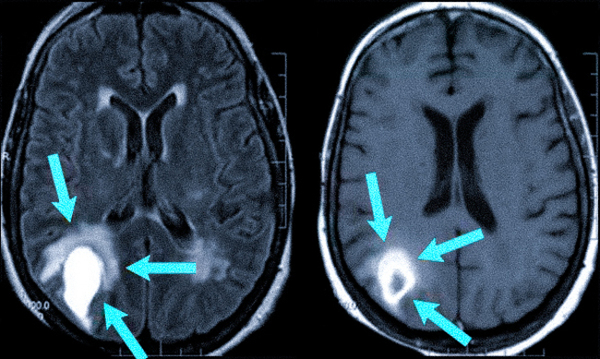

Одновременно с этим компьютерная томография позволяет получать послойные изображения вещества головного мозга. В зоне основания черепа хорошо видны ствол головного мозга и прилежащие костные ориентиры.

- внутричерепные повреждения мозговой ткани (ушибы, диффузное аксональное повреждение);

- кистозные изменения субарахноидального пространства, которые чаще всего выявляются на основании мозга;

- признаки гидроцефального синдрома.